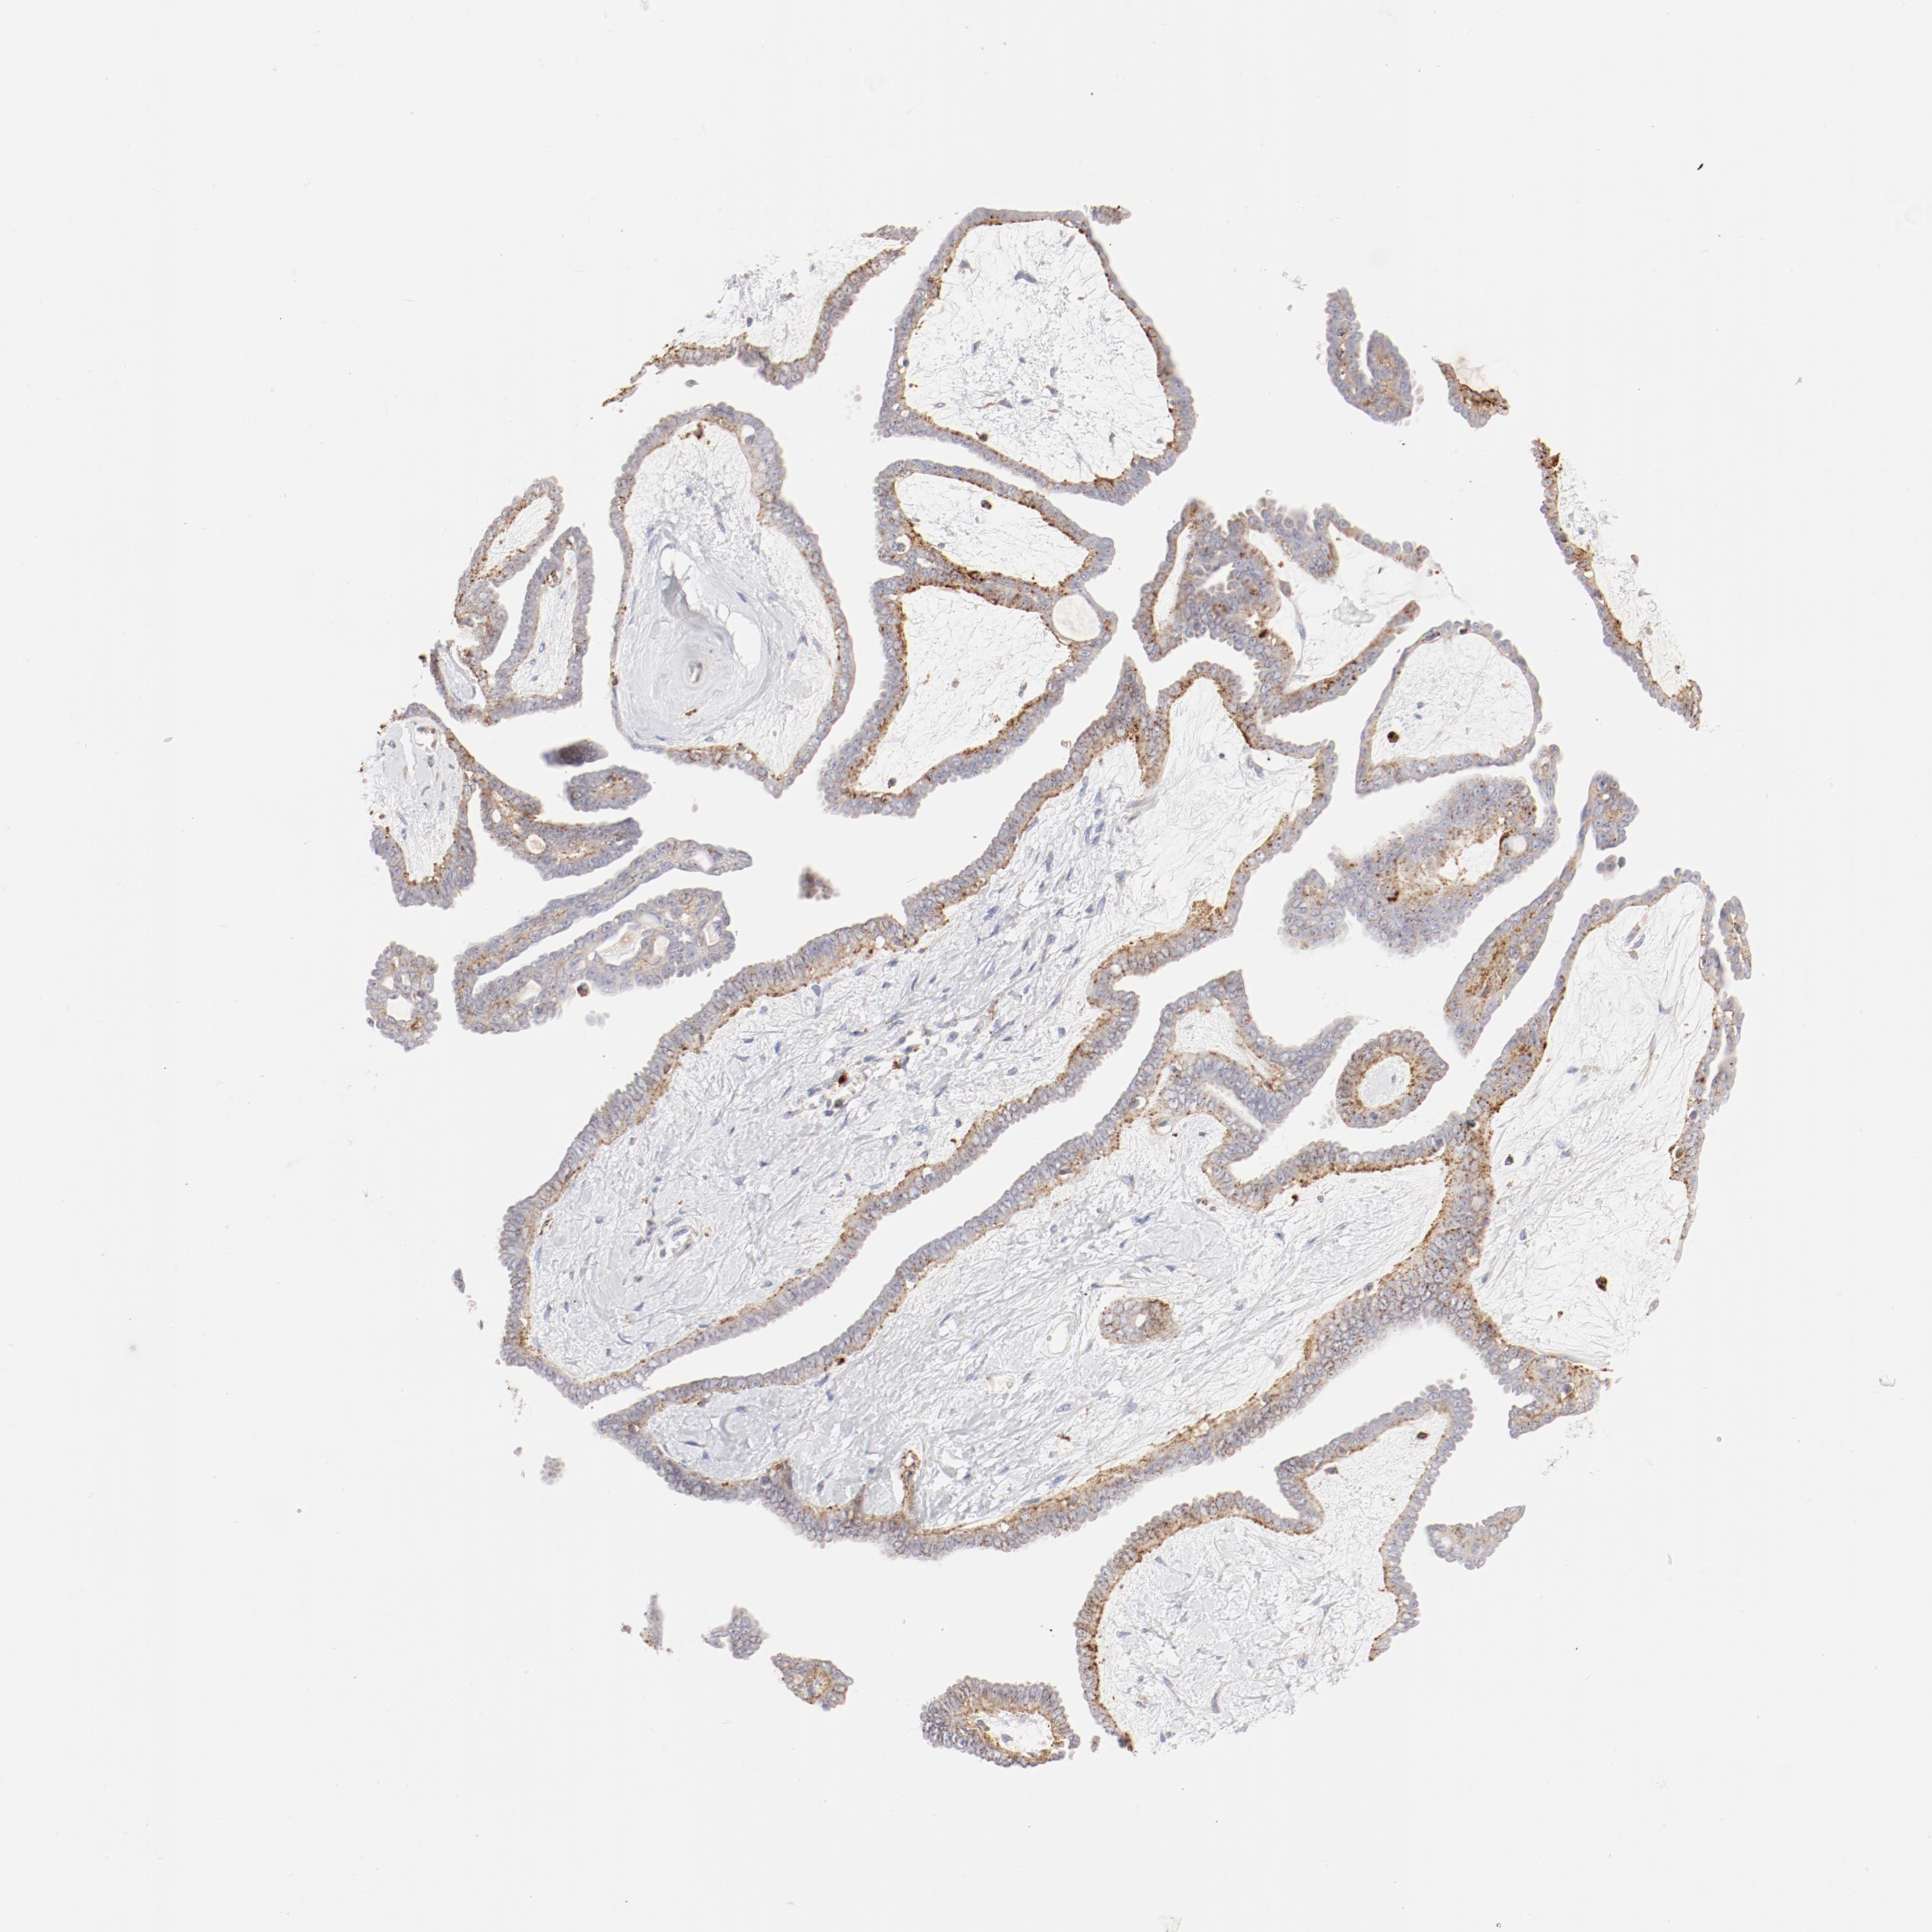

OVARIAN CANCER - Protein expressioni

A mouse-over function shows sample information and annotation data. Click on an image to view it in a full screen mode. Samples can be filtered based on level of antibody staining by selecting one or several of the following categories: high, medium, low and not detected. The assay and annotation is described here.

Note that samples used for immunohistochemistry by the Human Protein Atlas do not correspond to samples in the TCGA dataset.

Antibody stainingi

Antibody staining in the annotated cell types in the current human tissue is reported as not detected, low, medium, or high, based on conventional immunohistochemistry profiling in selected tissues. This score is based on the combination of the staining intensity and fraction of stained cells.

Each image is clickable and will lead to virtual microscopy that enables deeper exploration of all samples and also displays staining intensity scores, fraction scores and subcellular localization as well as patient and tissue information for each sample.

Antibody HPA003524

Antibody CAB000458

Cystadenocarcinoma, mucinous, NOS

Cystadenocarcinoma, serous, NOS